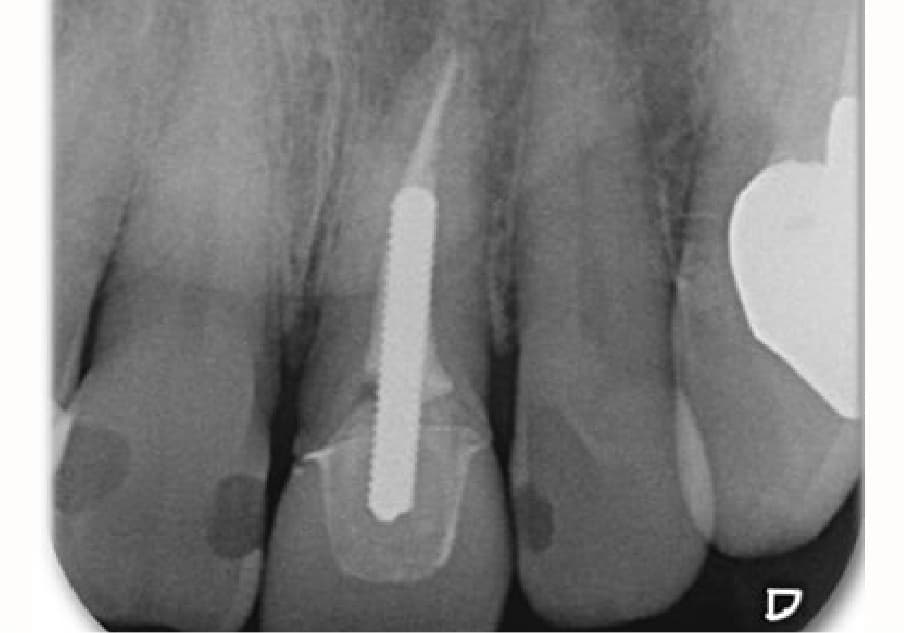

前歯の歯茎が腫れてきた

再根管治療の症例について

20年ほど前に転倒して歯冠破折、歯科を受診し抜髄、補綴処置を受けた。1ヶ月位前に腫脹を確認して歯科を受診、当院へ紹介されました。

| 主訴 | 前歯の歯茎が腫れている | 診断 | 慢性化膿性根尖性歯周炎 |

| 治療時年齢 | 57歳 | 性別 | 男性 |

| 治療期間/回数 | 1ヶ月ほど | 費用 | 22万円(税込み) ※紹介のため、補綴は行っておりません |

| 治療時の注意点 | 再根管治療となるので、必然的に初回の根管治療より、成功率が下がりやすい傾向があります。 ※自由診療の範囲となります。 |